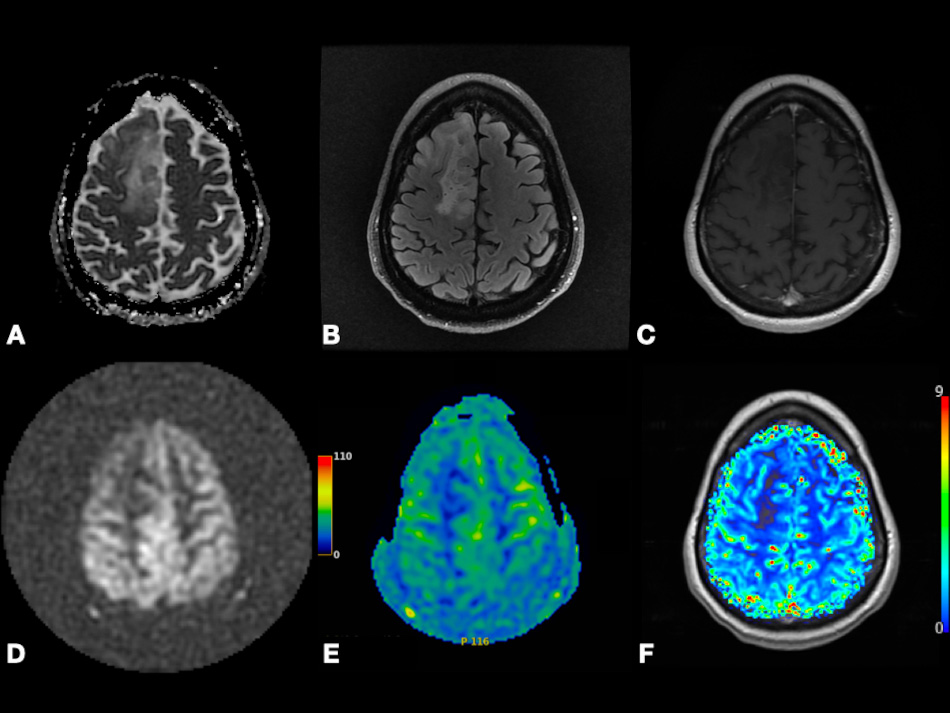

In contrast to conventional MRI, which delineates the anatomical structures and shows gross changes in the structure of the tumor, advanced MRI techniques represent dynamic physiological properties of tissue, which may be helpful in differentiating undiagnosed lesions based on properties including vascularity, cellularity, and metabolism [7, 8, 9]. The term advanced MRI techniques is used throughout this article to refer to dynamic contrast-enhanced (DCE) MRI, dynamic susceptibility contrast (DSC) MRI, diffusion-weighted imaging (DWI), arterial spin labeling (ASL) MRI, and blood oxygen level-dependent functional MRI (BOLD fMRI). In Figs. 1,2, we present different MRI images of two cases with different brain lesions including right frontal lobe oligodendroglioma (WHO grade II) and left lateral ventricle cavernous malformation. These two figures demonstrate the main differences between conventional MRI which delineates the anatomical borders of the brain lesions and advanced MRI techniques which demonstrate the internal physiologic features of different tumors, such as their vascularity, cellularity, perfusion, oxygenation, and microstructure.

Fig. 2.Left lateral ventricle cavernous malformation. Axial T2-weighted (A), pre- and post-contrast T1-weighted (B,C), and SWI (F) images depicting lesion with heterogenous enhancement, heterogenous predominantly hyperintense signal, peripheral hemosiderin rim, and extensive blooming. Axial pcASL source data (D) and color-coded CBF map (E) depicting no hyperperfusion. Abbreviations: SWI, Susceptibility weighted imaging; pcASL, Pseudo-Continuous Arterial Spin Labeling; CBF, cerebral blood flow.